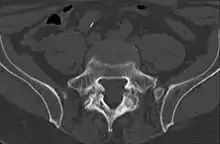

Computed tomography

Commonly known as a CT Scan or CAT scan, this form of imaging is very similar to x-ray technology but produces many more images than an x-ray does. The multiple images produce cross-sectional views not possible with an x-ray. This allows a physician or radiologist to examine the images from many more angles than an x-ray allows. For this reason the CT scan is much more accurate in detecting spondylolysis than an x-ray. Bone scintigraphy combined with CT scan is considered the gold standard which means that it is best at detecting spondylolysis.[13][15]